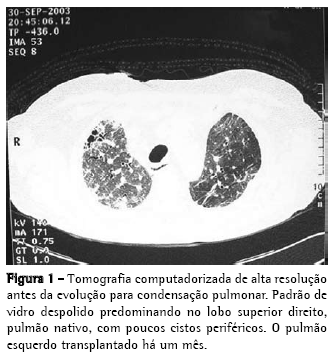

Homem, 56 anos, com diagnóstico de FPI (clínicofuncional-tomográfico-patológico) há cinco anos, evoluiu progressivamente com dispnéia a mínimos esforços e tosse mucóide escassa, intensa e de difícil controle. Apresentava, no mês do transplante pulmonar, hipoxemia e hipercapnia (PaO2 57 mmHg e pressão parcial de dióxido de carbono no sangue arterial 45 mmHg, em repouso e no ar ambiente ao nível do mar), DCO 29% do previsto, capacidade vital forçada 40,8% (1,41 L) e o volume expiratório forçado no primeiro segundo 52,6% (1,31 L). A cintilografia perfusional pulmonar demonstrava fluxo arterial de 76,7% para o pulmão direito e 23,3%, para o pulmão esquerdo. Os exames laboratoriais para o diagnóstico de doenças do colágeno e o inquérito epidemiológico para as doenças intersticiais conhecidas foram negativos. Durante os cinco anos de acompanhamento, tinha utilizado corticosteróides (prednisona 0,25 a 1 mg/kg/dia), imunossupressores (azatioprina ou ciclofosfamida 0,5 a 2 mg/kg/dia) e antifibrótico/imunomodulador (interferon-.1b) por quatro meses. O transplante foi unilateral à esquerda, correspondendo à menor perfusão arterial e maior intensidade do acometimento do interstício pela tomografia computadorizada de alta resolução (TCAR). No pós-operatório imediato evoluiu com instabilidade torácica devido à fratura de três arcos costais, em decorrência da tração de costelas osteopênicas durante o fechamento da ferida cirúrgica, e com isquemia de reperfusão pulmonar grave (relação PaO2/fração inspirada de oxigênio = 124). Permaneceu em ventilação mecânica (VM) invasiva por dez dias, traqueostomizado, e recuperando-se progressivamente da hipoxemia. O esquema de imunossupressão iniciado foi composto pela ciclosporina 5 mg/kg de 12/12 h, prednisona 0,5 mg/ kg/dia e azatioprina 2 mg/kg/dia, além do anticorpo anti-receptor da interleucina-2 basiliximab no 1º e 4º dias pós-operatório e da metilprednisolona 1 g no pré-operatório. Obteve alta da unidade de terapia intensiva para o quarto da unidade semi-intensiva, mas no 8º dia na unidade semiintensiva houve exacerbação da dispnéia, associada ao retorno da tosse seca e de progressiva estertoração crepitante em todo o hemitórax direito, sendo re-encaminhado para a unidade de terapia intensiva. Uma nova avaliação foi feita através de TCAR, broncofibroscopia com lavado broncoalveolar (LBA) e biópsia transbrônquica do lobo inferior esquerdo e do lobo superior direito. Todas as culturas foram negativas, o LBA tinha padrão neutrofílico, sem eosinófilos ou macrófagos com hemossiderina, e o histopatológico não foi conclusivo. Foi realizada arteriografia pulmonar e, posteriormente, vídeotoracoscopia com biópsia pulmonar em três diferentes regiões do lobo superior direito para assegurar a representatividade da doença (Figuras 1 e 2). A arteriografia não demonstrava doença tromboembólica.

As imagens radiográficas demonstravam condensação dos lobos médio, superior e inferior direito, e o diagnóstico estabelecido foi de exacerbação da FPI no pulmão nativo, caracterizado principalmente pelo aspecto histológico de PIU (infiltrado não-uniforme e multifocal, com espessamento inflamatório e fibroso do interstício alveolar, cistos pulmonares, fibrose peribronquiolar, hiperplasia alveolar e ausência de membranas hialinas) e pelas ausências de crescimento microbiano nos tecidos pulmonares e de descompensação cardiovascular. Sabe-se que na FPI, o pulmão se torna progressivamente colapsado, o que pode simular imagens de condensações pulmonares. A variante acelerada da FPI está sendo recentemente descrita e deve ter o seu diagnóstico caracterizado pela exclusão de outras causas de exacerbações. A literatura menciona, no transplante pulmonar unilateral, a progressão crônica da FPI no pulmão nativo, não havendo relatos de progressão aguda. Este é o primeiro caso da literatura nacional descrito como FPI na sua fase acelerada.